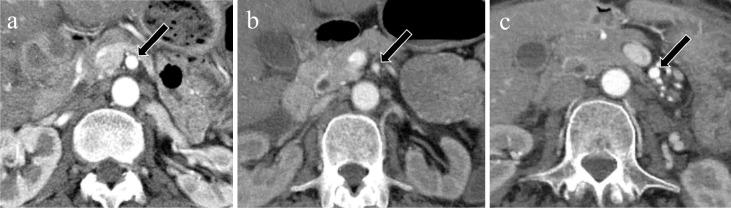

Acute mesenteric ischemia is a life-threatening condition. A comprehensive approach involving a multidisciplinary team to review patient background, clinical history, physical examination, laboratory data, and imaging examination for respective diagnosis of superior mesenteric arterial occlusion, nonocclusive mesenteric ischemia, and superior mesenteric venous occlusion is essential. The most important imaging modality is computed tomography, which is used for diagnosis and for directing therapeutic strategy (e.g., endovascular revascularization, surgical bowel resection, or conservative management). Computed tomography image findings can support triaging of irreversible transmural bowel necrosis compared with reversible ischemic change with reperfusion. In this review article, the computed tomography imaging findings specifically associated with the pathophysiology of superior mesenteric arterial occlusion, nonocclusive mesenteric ischemia, and superior mesenteric venous occlusion are reviewed.

急性肠系膜缺血是一种危及生命的疾病。采用多学科团队的综合方法来审查患者背景、临床病史、体格检查、实验室数据以及影像学检查,以分别诊断肠系膜上动脉闭塞、非闭塞性肠系膜缺血和肠系膜上静脉闭塞至关重要。最重要的影像学检查方法是计算机断层扫描,它用于诊断并指导治疗策略(如血管内血运重建、手术肠切除或保守治疗)。计算机断层扫描图像结果有助于区分不可逆的透壁性肠坏死与可通过再灌注逆转的缺血性改变。在这篇综述文章中,将对与肠系膜上动脉闭塞、非闭塞性肠系膜缺血和肠系膜上静脉闭塞的病理生理学具体相关的计算机断层扫描影像学结果进行综述。